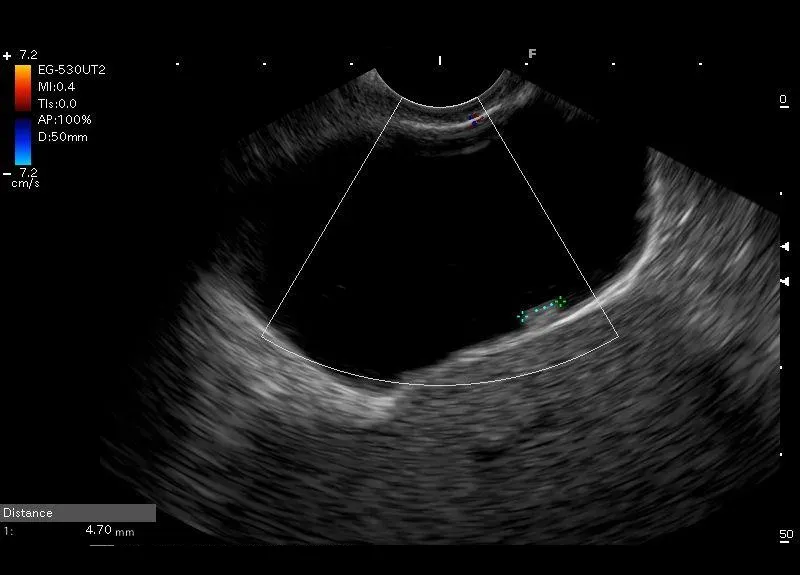

Drobna, przylegająca do ściany pęcherzyka struktura, bez widocznego cienia akustycznego, która nie przemieszczała się podczas próby wstrząsania- drobny polip pęcherzyka żółciowego